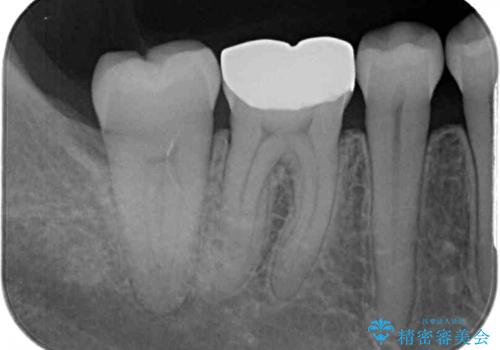

- 人と話す際に、下顎の奥にある銀歯が目立って気になるとのことで来院された患者様です。

左右の奥歯に銀歯のクラウンが装着されていたため、銀歯除去後に仮歯に置き換え、フルジルコニアクラウンにて補綴治療を行うこととしました。

フルジルコニアクラウンは、やや光沢のある材質ですが、奥歯に装着した場合にはさほど気にならず、自然な口元の印象となりました。